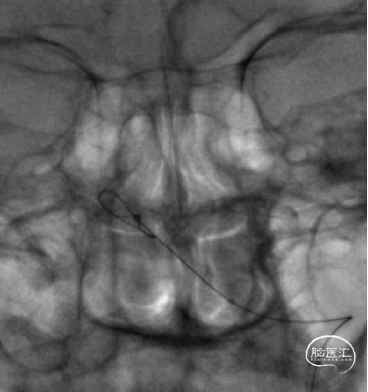

术后影像:

术后3月余复查:

动脉瘤愈合,支架内血流通畅。